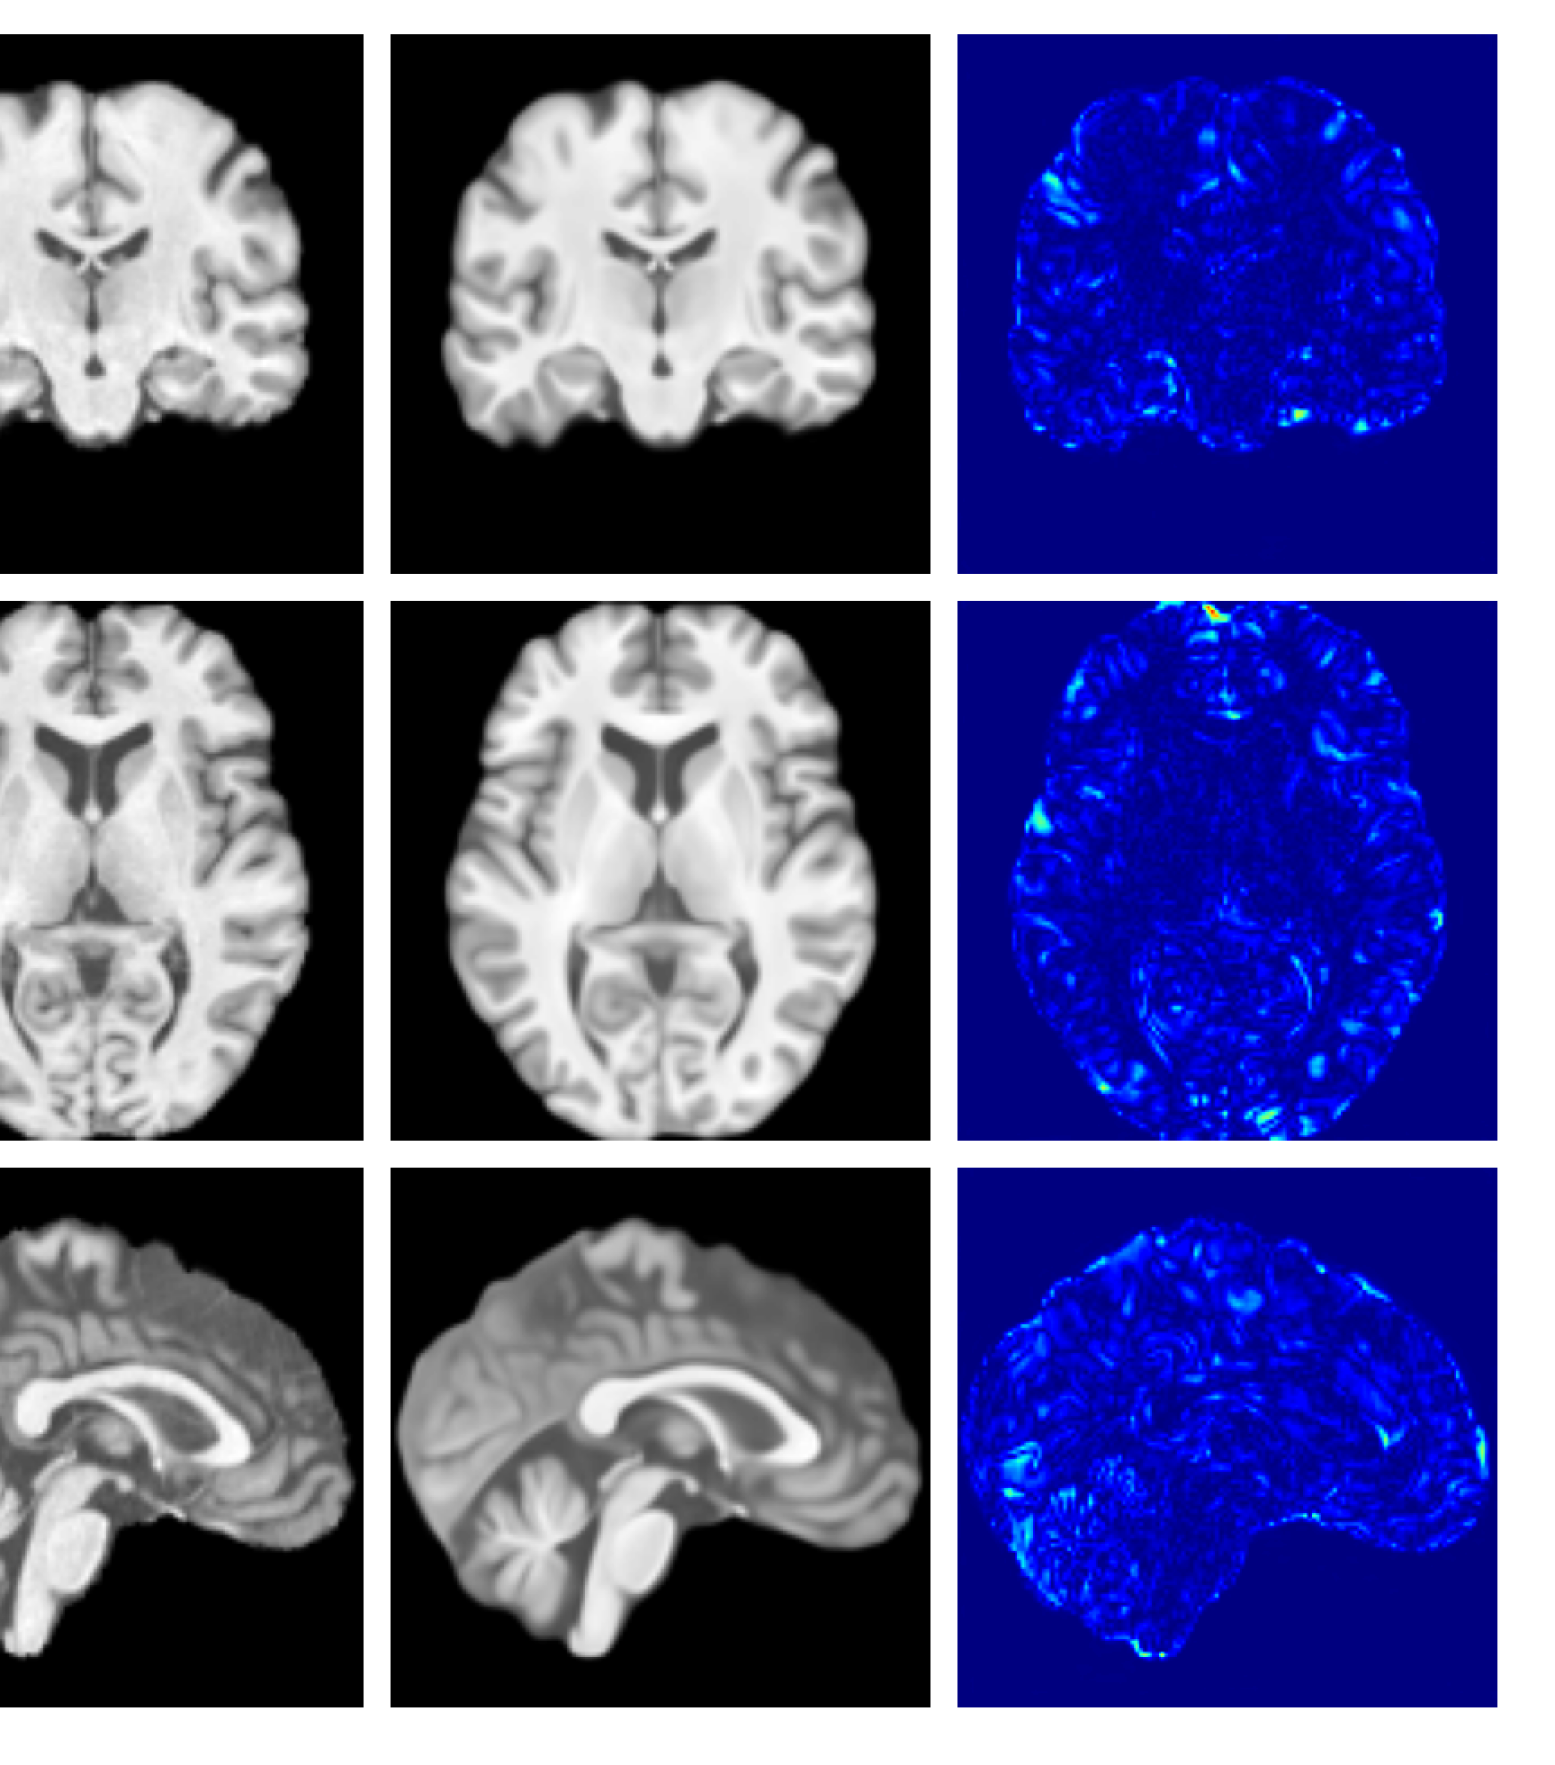

Figure 4: Example reconstructions and anomaly maps from a disease cohort sample in the UoTH dataset, shown for the top three models. The lesion is highlighted in red in the original image.

For the UoTH dataset, Table 2 shows that whilst CADD outperforms all other DDPM methods, it is outperformed by the VAE and cVAE models. Unlike the UKBB and ADNI datasets, the UoTH dataset contains noisy images with larger lesions and regions of pathology. Here, the CADD threshold, which limits the number of regions flagged as anomalous at each inpainting step, may be too stringent to fully inpaint extensive anomalies. It should be noted, however, that the improved disease detection performance of the VAE and cVAE models comes at the cost of accurate reconstruction of healthy tissue as illustrated in Table 1 and Figure 4. Such poor quality reconstructions would not be suitable for downstream tasks such as anomaly segmentation or image processing algorithms.

Figures 8 and 9 are enlarged versions of Figures 3 and 4 respectively, with the latter now including results from all compared methods. Figure 10 provides example reconstructions and anomaly maps for an AD subject from the ADNI disease cohort.

Figure 9: Enlarged example reconstructions and anomaly maps for a sample from the disease cohort of the XXXH dataset. The lesion region is indicated in the original image by the red box.